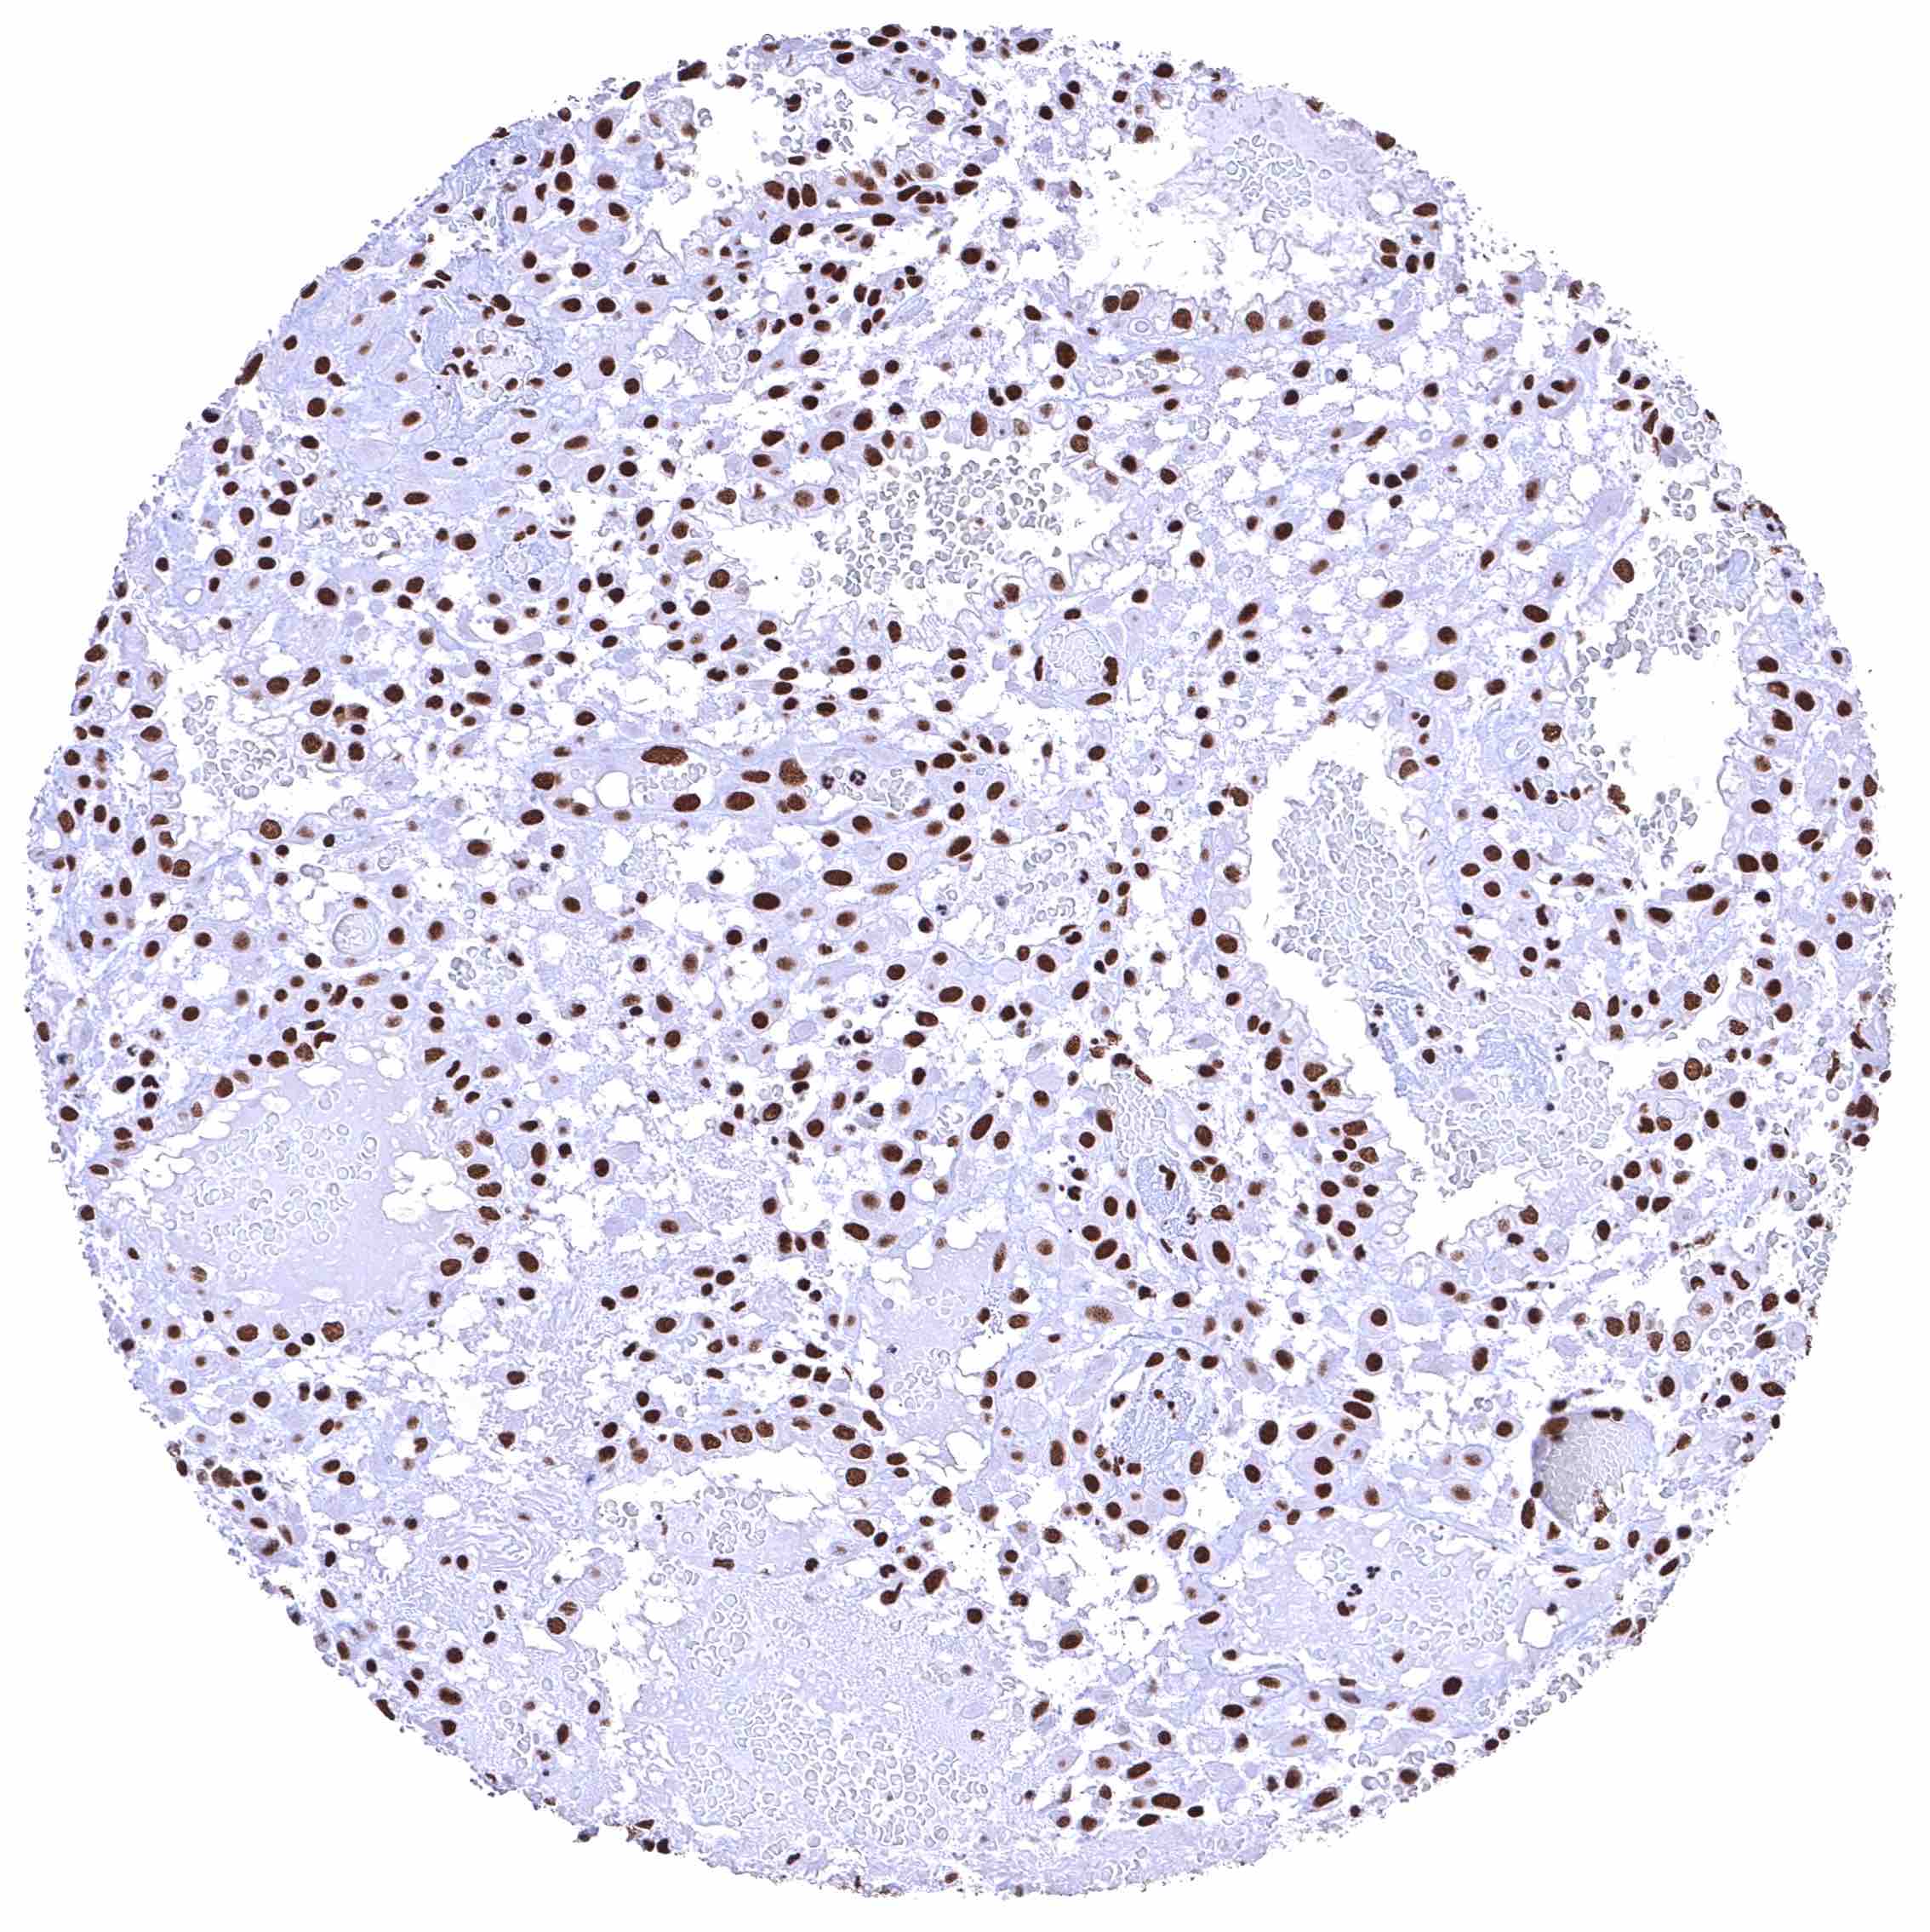

Lung